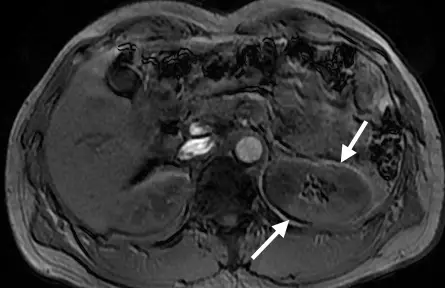

- 影像為腹部之軸切面(Axial view)MRI 影像(無脂肪抑制),圖中可見肝臟、脾臟、腹主動脈以及雙側腎臟等解剖構造。

- 圖中白色箭號標示出左腎(位於影像右側)的前後邊緣,該處為腎臟(富含水分)與後腹腔脂肪(富含脂肪)的交界處。

- 上方箭號指向左腎的前側邊緣,可見一條清晰的黑色低訊號帶(Signal void / dark band)。

- 下方箭號指向左腎的後側邊緣,可見一條相對應的白色高訊號帶(Signal overlap / bright band)。

- 這種在單一器官相背對的兩側,分別出現「一暗、一亮」邊界的典型視覺表現,是發生於頻率編碼方向(Frequency-encoding direction)上的第一型化學位移假影(Chemical shift artifact of the first kind; Spatial misregistration)。由此可推知,此張影像的頻率編碼方向設定為前後向(Anteroposteri